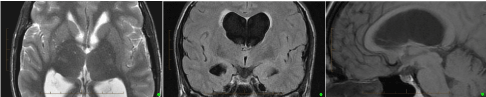

Figure 2: Preoperative MRI scan from Left to Right - Transverse T2, Coronal FLAIR & Sagittal T1 (non-contrast). These show acute hydrocephalus with indistinct anatomy in the anterosuperior aspect of the 3rd ventricle. View Figure 2